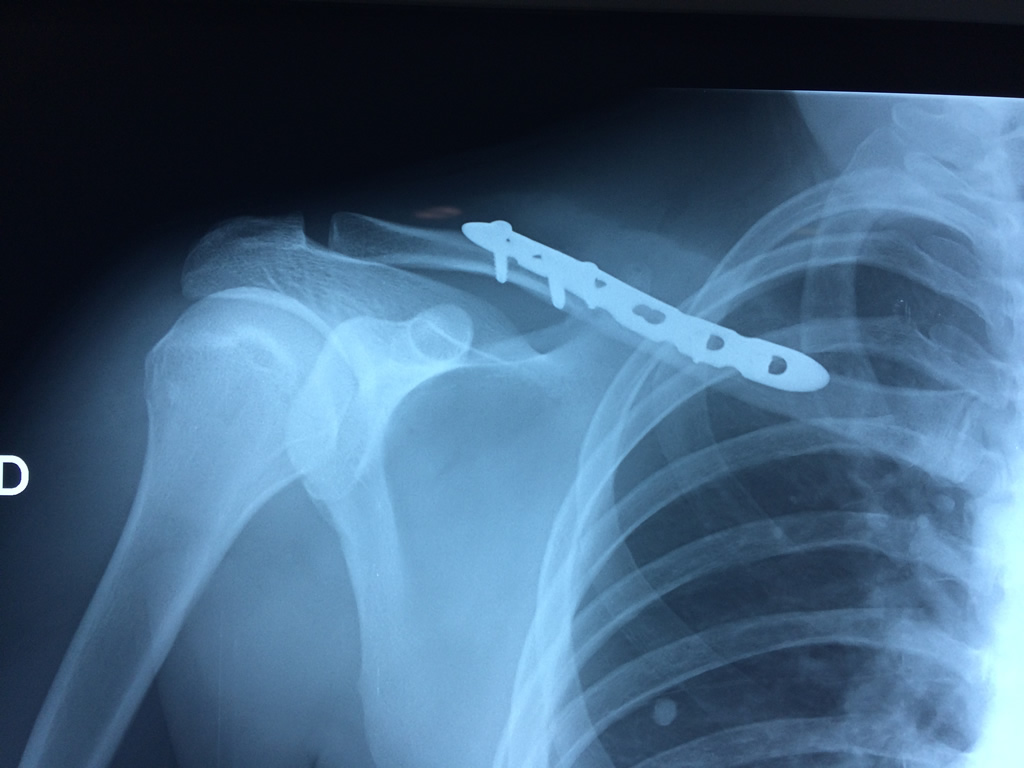

Clavícula

La clavícula es un hueso largo, con forma de "S" itálica, situado en la parte anterosuperior del tórax. Junto con la escápula forman la cintura escapular. Se puede palpar por toda su longitud y se extiende del esternón al acromion de la escápula, siguiendo una dirección oblicua lateral y posterior.